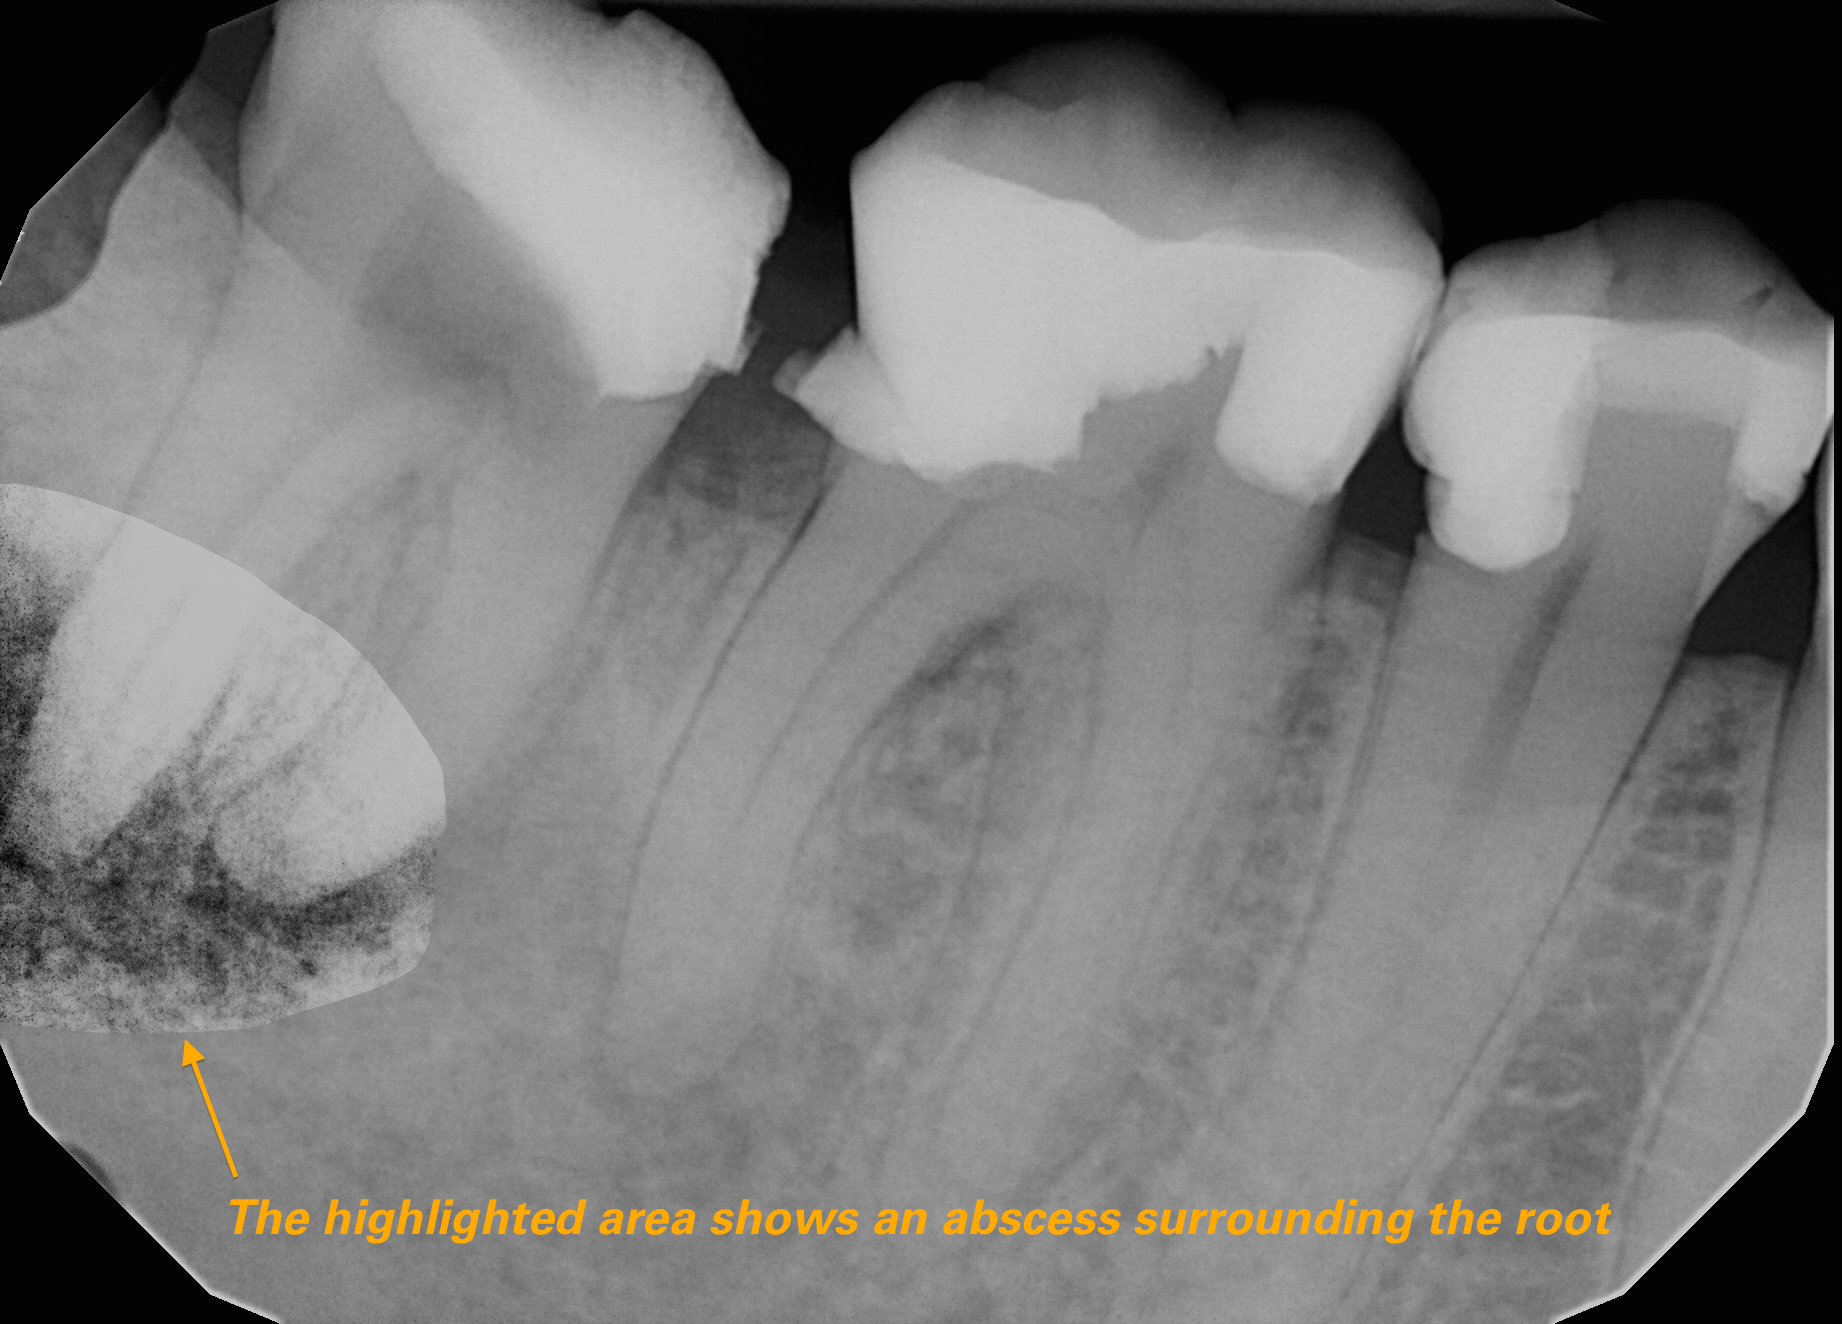

Discover how an Xray in pneumonia serves as a vital diagnostic tool. Learn how chest imaging identifies lung inflammation, infiltrates, and consolidation to confirm a diagnosis. This guide explains the role of radiographic findings, imaging accuracy, and clinical interpretation in detecting pulmonary infections, helping patients and providers understand the essential process of visualizing pneumonia on an X-ray.